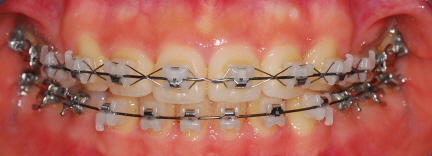

<정면 사진>

<하악사진> 저는 처음에 왜 다시 벌어지지? 하고 걱정했는데 치과선생님께서 벌리는 것이 더 어렵다고 하셨어요~ 의도된 과정이었더라구요*^^* 이번달은 고무줄을 다시! 이용하여 윗니는 뒤로 아랫니는 앞으로 당겨주는 작업을 할거에요 그래서 고무줄은 위아래로 걸게 되었습니다~ 밥먹을 때 마다 뺏다 꼈다 해야 하는데 오랜만에 다시 고무줄끼니 정말....아프네요 맛잇는거 있어도 못먹고.. 옛날에 엄마가 치아가 많이 빠져서 딱딱한거 먹는 저랑 동생들 보면서 밥먹을때마다 부럽다고 하셨었는데 지금 제가 그러니 진짜 부럽고.. 엄마께 미안한 마음도 들고 그래요..ㅠㅠ

아아 쨋든 이번달 과정은 고무줄이구요 한가지 더~ 윗니가 예전사진을 보면 앞니 뒤가 많이 울퉁불퉁 한 것을 볼 수 있는데요 윗니와 아랫니가 서로 좀 더 가깝게 하기 위해 뒷부분을 좀 깎는 작업을 했습니다 치과쌤의 표현 방식을 빌리면 일종의 배가 나온 부분을 다이어트 시켰다고나 할까요?!ㅎㅎㅎㅎ (내 배도좀 해야될듯....)